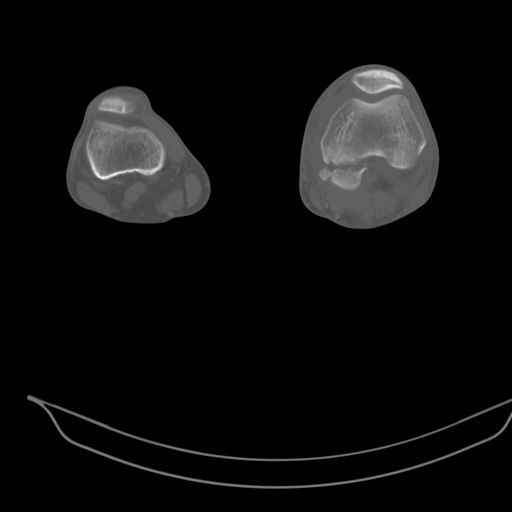

Качественные только исходные рентгенограммы (вышлю или завтра или в понедельник). Все последующие рентгенисследования были малоинформативны

(в т.ч. и последние снимки). КТ-исследование делалось 3 или 4 дня назад...

This is a coronal split in the femoral condyle and is a rare injury. Please see attachment for ORIF result

CT shows major bony fragments which are markedly rotated .With this amount of bony damage,you probably should attempt to get reasonably loooking knee with ORIF and thn if he needs a TKR due to pain a few years from now, then tleast you have something looking like a knee that you can replace rather than having to use revision knee for a primary TKR now. 4 weeks is not too long .what is the condition of soft tissues?

При внутрисуcтавных переломах трехмерные (3D) изображения, кроме красивого снимка, не дают полную информацию о состоянии отломков, самыми информативными являются корональные срезы на КТ и обычная длинная ренгенограмма конечности для сравнения оси конечности.

Фронтальные внутрисуставные переломы мыщельков бедра, так называемые Hoffa fracture, не частые, но встречающиеся переломы, в основном они связаны с травмой высокой энергией.